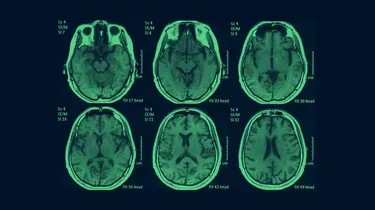

Régulièrement, la presse se fait l’écho d’histoires de nourrissons morts ou handicapés, toutes plus sordides les unes que les autres. Quasi automatiquement, le père, la mère ou la nounou — la dernière personne à avoir tenu l’enfant — se retrouve soupçonnée de l’avoir secoué violemment, dès que des épanchements de sang au cerveau sont constatés. En France, les cas signalés à la justice et les condamnations se multiplient, au point que certains parlent « d’épidémie de bébés secoués ». Si la maltraitance est dans certains cas avérée, il y a aussi et souvent d’autres causes, médicales, qu’on oublie de chercher ou qui sont réfutées. Un récent procès, qui vient de s’achever, illustre cette mécanique infernale.